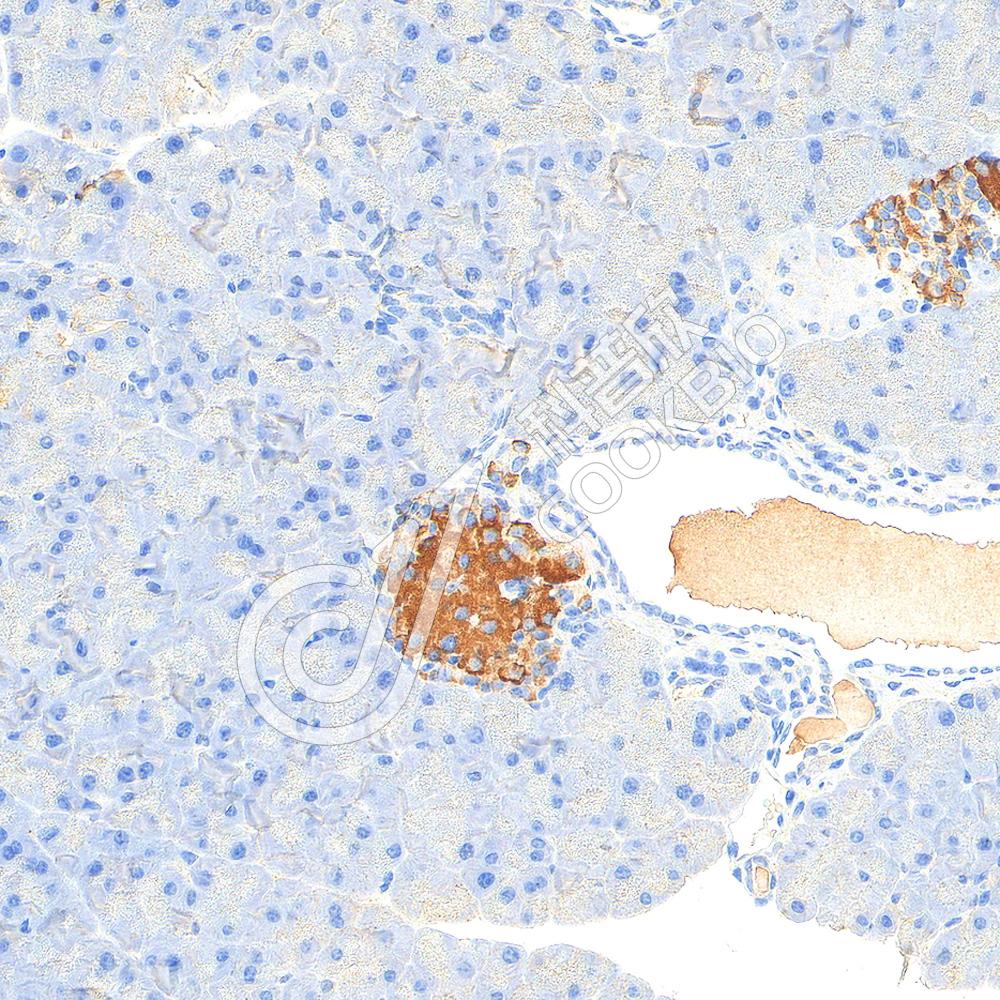

IHC检测GAD65蛋白(货号 K5450084).

样品: 小鼠胰腺, 4%多聚甲醛 (货号KSG1101) 固定12-24小时.

抗原修复: Tris-EDTA抗原修复液(pH 9.0) (KSG1203), 98℃, 20分钟.

—抗: 1: 1500稀释, 4℃ 孵育过夜.

二抗: S-vision免疫组化多聚二抗(山羊抗兔),即用型 (货号KB3906), 室温孵育20分钟.